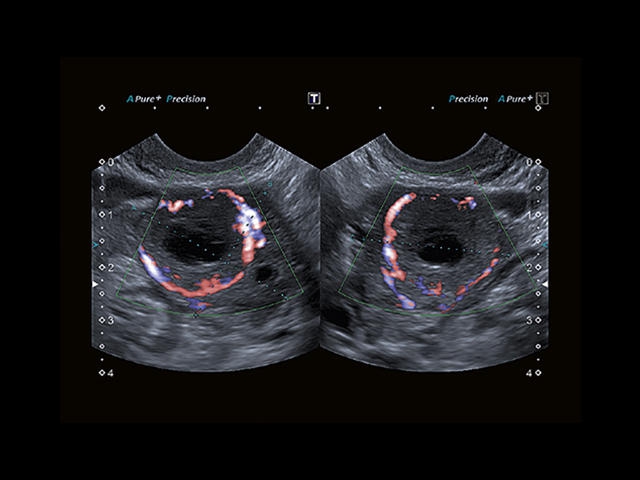

Обновленная версия легендарного УЗ-сканера. Стационарный аппарат экспертного класса Aplio 500 Toshiba NEW, визуализирует анатомические структуры в высоком разрешении. Модель позволяет выявить микрокальцификаты, новообразования, нарушения в работе сердца, сосудов и мышц. Присутствует функция виртуальной эндоскопии, 4D-сканирования, эластометрии тканей, УЗИ с контрастированием. За повышение качества изображения отвечают технологии ApliPure и Superb Microvascular Imaging. Первая задействует возможности пространственного и частотного кодирования, формирует цельный визуальный ряд с сохранением клинических маркеров. Вторая улучшает отображение микрососудистого русла, используя доплеровский эффект. Модель оснащена 21-дюймовым монитором, имеет 4 активных порта. Возможно подключение педиатрических, интраоперационных, лапароскопических и чреспищеводных датчиков.

Трехмерная реконструкция ЦДК:

Да

Цветовой допплер: